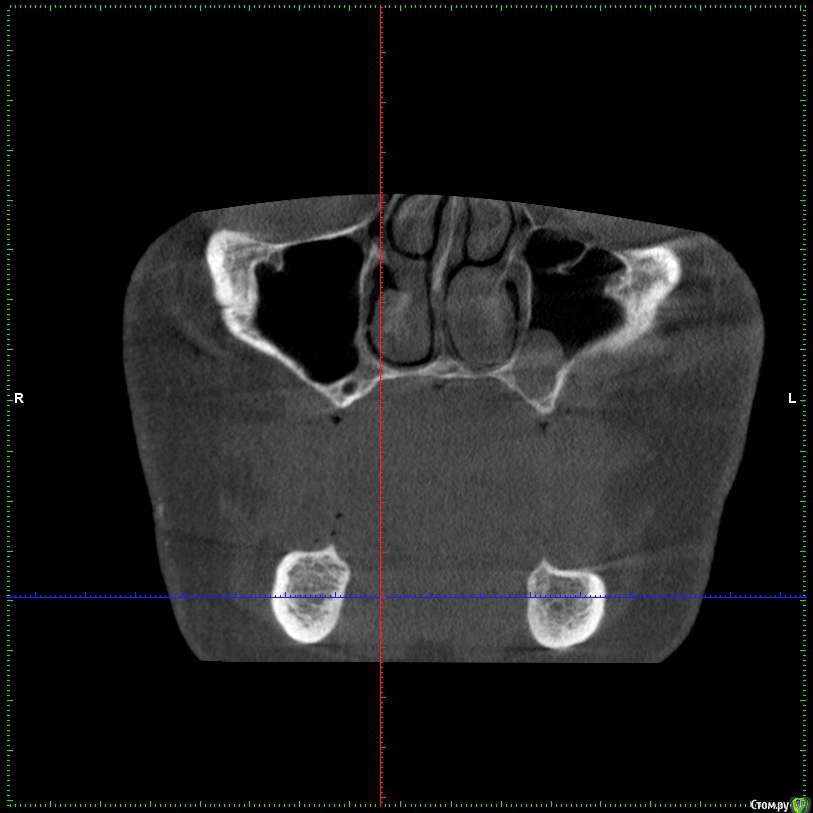

Aleksey_Mironov Опубликовано 11 января, 2018 Автор Поделиться Опубликовано 11 января, 2018 здравствуйте коллеги!! вот такой сюрприз..хочу сделать синус лифтинг.. что за образование можеть быть? Ссылка на комментарий

Борис80 Опубликовано 11 января, 2018 Поделиться Опубликовано 11 января, 2018 Не совсем уверен, тк недостаточно срезов видно, но я бы сказал насморк или что-либо подобное(это по поводу тени) и , что значительно неприятнее, это костная перегородка на дне пазухи Ссылка на комментарий

колесников Опубликовано 11 января, 2018 Поделиться Опубликовано 11 января, 2018 (изменено) Может образоваться перфорация мембраны. Делайте 2 окна Изменено 11 января, 2018 пользователем колесников Ссылка на комментарий